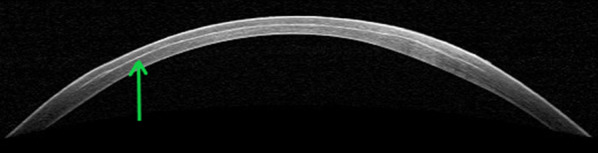

Eyes are examined using OCT imaging of the cornea to show that the laser pattern was delivered to the pre-programed trajectory location for each pattern segment confirming uniformity of depth and symmetry of placement (Fig. 1). Corneal topography imaging is another useful tool that can detail corneal curvature changes post surgery. In vivo corneal topography imaging was previously studied by the authors in the rabbit model using a Pentacam HR Scheimpflug camera to better understand corneal biometric measurements (Gray et al. Invest Ophthalmol Vis Sci. 2010;51:ARVO E-Abstract 4200). Effectiveness of the laser treatment is further evaluated through the manipulation of lenticle or flap (either the lenticule is extracted or the corneal flap is lifted) to evaluate ease of tissue separation (flap) and for ease of lenticule removal. A successful treatment occurs when the tissue manipulation does not disturb any collateral tissues. Tissue separation (cleavage) performed by the laser is a key factor for healing; if not cleaved well, tearing of tissues may occur leading to an extended healing process. It is critical to assess the completeness of tissue separation, as incomplete separation and tearing may impact stromal tissue causing higher order aberrations and visual degradation. This assessment may be accomplished by evaluation of adhesion levels and ease of separation during the surgical procedure and then adjusting laser settings as needed. Measurement of wavefront aberrations is another method that may be used to assess the cornea post surgery that has been previously performed in the rabbit model in vivo by the authors using a Wavescan Wavefront System [26].

Fig. 1.

OCT image of cornea immediately post laser treatment with lenticule removed. Green arrow indicates post laser lamellar bubbles. The image allows assessment of collateral tissue effects of the laser pulse as well as laser pulse depth and location